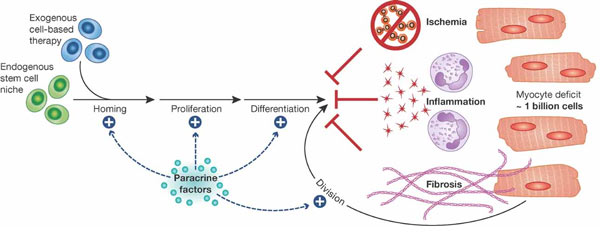

কোষ, কলার রিজেনারেশনের পথগুলি...

জেব্রাফিশের হার্টের কোষ, কলার রিজেনারেশনের ধাপগুলি

ইঁদুরের হার্টের কোষ, কলার রিজেনারেশনের ধাপগুলি

ইঁদুরের হার্টের কোষ, কলার রিজেনারেশনের ধাপগুলি

রিজেনারেশনের ধাপ (জেব্রাফিশ, ইঁদুর, মানুষ)